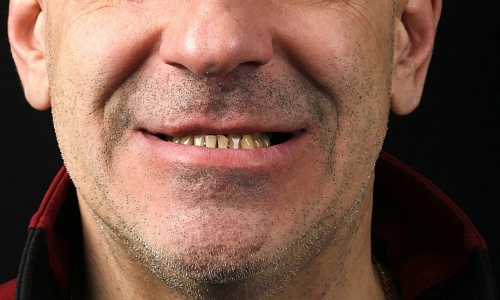

до

после

Мезиальный прикус. Дефицит места для зубов верхней челюсти. Лечение на брекетах Damon-Q. Без удаления зубов. Срок лечения 1,5 года.